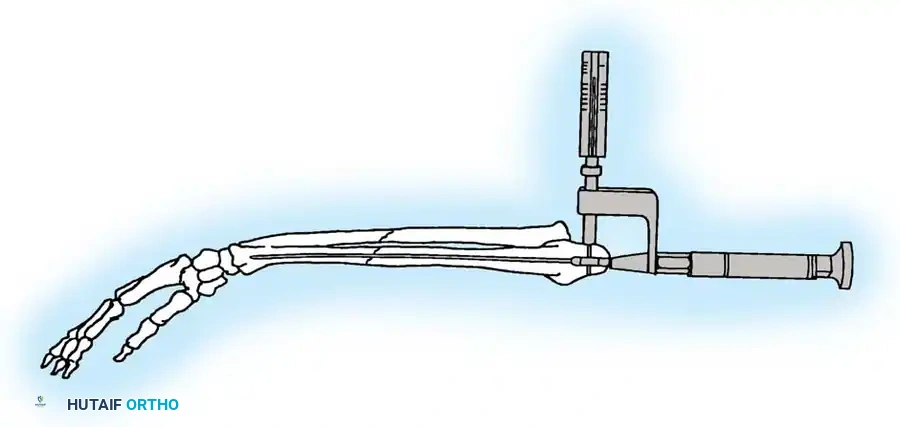

4. Plate Osteosynthesis

If comminution with bone loss prevents the use of a tension band compression technique—due to the risk of shortening the olecranon and narrowing the greater sigmoid notch—plate fixation is mandatory. Plating is also the gold standard for Monteggia fracture-dislocations, oblique fractures extending distally, and fractures involving the coronoid process.

Construct Design:

Hand-contoured reconstruction plates or modern, anatomically precontoured locking plates (e.g., Acumed, Synthes) provide rigid, stable fixation. The plate is applied to the posterior (tension) surface of the ulna.

🔪 Surgical Technique: Plate Fixation

- Reduction: Restore the articular block. Temporary K-wires can be used to hold comminuted articular fragments.

- Plate Application: Apply a precontoured olecranon plate to the posterior aspect of the proximal ulna. The proximal portion of the plate often wraps over the tip of the olecranon to capture the proximal fragment with multiple locking screws.

- Fixation: Secure the plate distally to the ulnar shaft using standard cortical or locking screws. If an oblique fracture line is present, a lag screw can be placed independently or through the plate to achieve interfragmentary compression.

- Bone Grafting: If significant metaphyseal void exists after elevating impacted articular fragments, autogenous cancellous bone graft or allograft should be packed into the defect prior to final plate tightening.